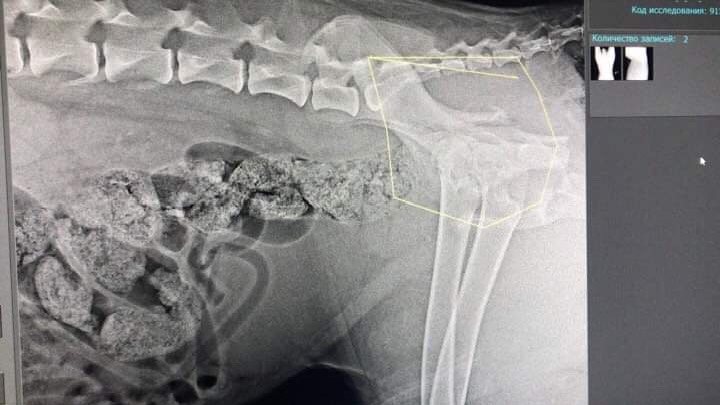

Двойной перелом таза без смещения. Чипа нет. Клеймо не рассмотреть -очень волосатое брюхо.

"надо показать снимки собаки специалистам,перелом со смещение,может надо оперировать и ставить пластину"

Обязательно надо но только после восстановления от пирика. А за эио время уже может успеть непоавильно сростисьДайвер писал(а):Мила, а что с тазом, оперировать не надо?

Фауста прооперировали